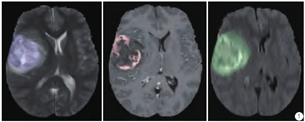

所有图像根据相同的标准由1~4个人进行分割,并由经验丰富的神经放射学家验证。总共分为4个区域,即:增强的核心(enhanced core)、水肿(edema)、非增强的实性核心(non-enhancing solid core)和坏死/囊性核心(necrotic/cystic core),区域之间没有重叠。数据集中将坏死/囊性核心与非增强的实性核心合并为一个区域,简称为NET区域,以感兴趣区(region of interest,ROI)NET表示。增强的核心区域和水肿区域分别简称为ET区域和ED区域,以ROIET、ROIED表示。图1为BRATS2017数据集中一例患者的胶质瘤示意图,蓝色为T2加权像上显示的整个肿瘤区域,即NET区域、ET区域、ED区域的总和;红色为增强T1加权像上显示的ET区域,绿色为FLAIR像上显示的水肿区域,即ET区域与ED区域的总和。